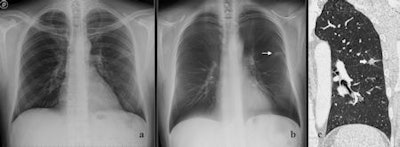

| Images of a peripheral lung nodule in a 65-year-old man. Posteroanterior radiograph (a) in the upright position shows one barely visible left lung nodule. Tomosynthesis image (b) shows the same nodule (arrow) as seen on the posteroanterior radiograph in (a) with a much higher conspicuity and with evidence of peripheral spiculations. CT image (c) (lung window, coronal plane reformation) confirms the left lobe nodule seen in (b) with evidence of peripheral spiculations. Images courtesy of Emilio Quaia, MD. |